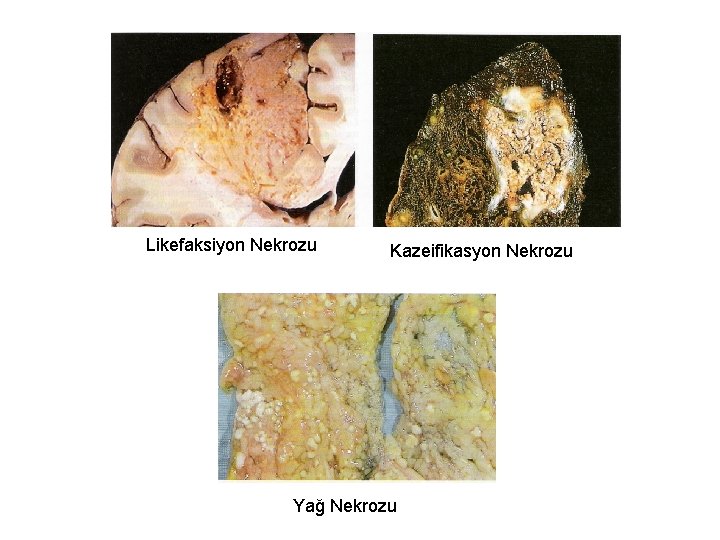

Nekroz tipleri: • Koagülasyon nekrozu (Beyin dışı dokularda, hipoksiye bağlı hücre ölümünün karakteristik görüntüsüdür. ) Doku çatısı bir süre de olsa korunur. • Likefaksiyon nekrozu (Beyinde hipoksiye bağlı hücre ölümünün karakteristik görüntüsüdür + Enfeksiyöz durumlarda) • Kazeifikasyon nekrozu (Ör: tüberküloz) • Yağ nekrozu (yağ dokusunu oluşturan hücrelerin ölümündeki görüntüdür. )

Likefaksiyon Nekrozu Kazeifikasyon Nekrozu Yağ Nekrozu